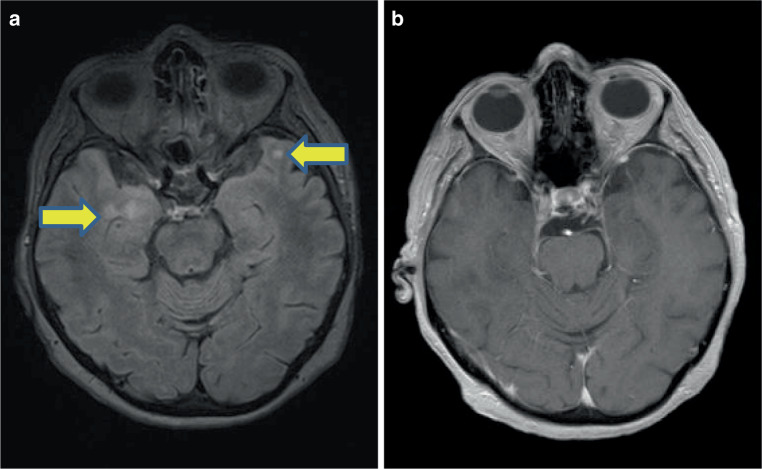

Case report: We present an anti-Ri antibody-positive 77-year-old woman with subacute progressive bilateral cranial nerve VI palsy, gait disturbance and jaw dystonia. MRI of the brain showed hyperintense signals on T2 bitemporal without contrast enhancement. Cerebrospinal fluid (CSF) examination exhibited mild pleocytosis of 13 cells/µl and positive oligoclonal bands. CSF was overall inconspicuous for a malignant or inflammatory etiology. Immunofluorescence analysis revealed anti-Ri antibodies in both serum and CSF. Subsequent diagnostic work up resulted in a newly diagnosed ductal carcinoma of the right breast. PNS in this case partially responded to the anti-tumor therapy.